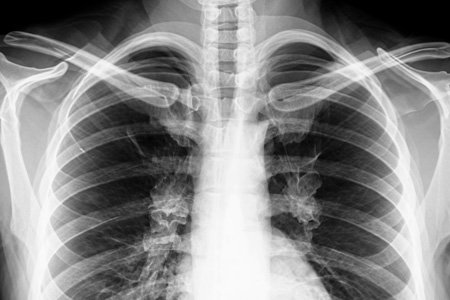

Влияние вейпов на лёгкие

Больные легкие

В отличие от сигарет, вейпы не создают дым, но это не значит, что их пар безопасен для дыхательной системы. Аэрозоль, который вдыхает пользователь, содержит мельчайшие частицы химических веществ. Они проникают глубоко в альвеолы – самые чувствительные участки лёгких, где происходит газообмен, вызывают микровоспаления уже после нескольких недель регулярного использования.

Организм воспринимает эти частицы как чужеродные и запускает защитную реакцию: слизистая бронхов утолщается, вырабатывается больше слизи, возникает хронический кашель. Это похоже на медленное раздражение дыхательной системы изнутри. В подростковом возрасте, когда лёгкие ещё развиваются, такие изменения могут повлиять на дыхательную функцию на всю жизнь.

В более тяжёлых случаях врачи фиксируют химический бронхит, пневмониты и редкое, но грозное осложнение – облитерирующий бронхиолит, или «попкорновую болезнь». Это воспаление и рубцевание мелких дыхательных путей, которое приводит к стойкой одышке, даже в покое. Болезнь необратима, может прогрессировать даже после полного отказа от парения.

«Мы видим молодых пациентов с кашлем и одышкой, которые никогда не курили сигареты – только вейпы. Их лёгкие выглядят так, будто они десятилетиями работали на вредном производстве», – рассказывает врач-пульмонолог Арсений Шульман.

Дополнительный риск – аллергические реакции. Ароматизаторы и остаточные металлы из испарителя вызывают отёк слизистой, затруднение дыхания, приступы у людей с астмой или чувствительными бронхами.

Всё это развивается не молниеносно, а постепенно, поэтому многие не связывают вейп с постоянной заложенностью, частыми простудами и слабостью. Последствия парения включают появление хронических патологий дыхательной системы – астмы, ХОБЛ, пневмоний.